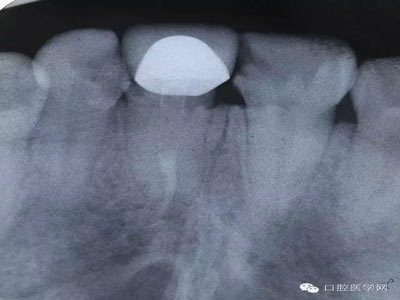

術(shù)前X片照,根尖情況尚可